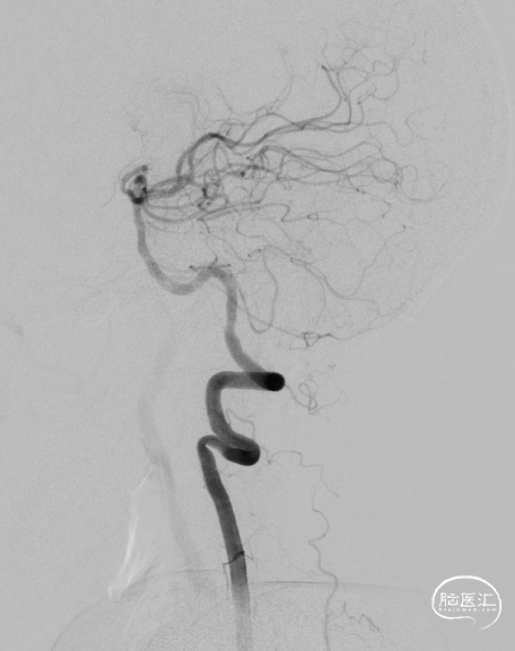

随访:患者术后一般情况好,无TIA再次发作。神经系统查体无明显异常,血压控制良好。

该患者双侧椎动脉起始段均狭窄,左侧更为严重,为闭塞前病变。为预防致死致残性脑卒中,行左侧椎动脉起始段支架植入术。选择Bridge椎动脉雷帕霉素靶向洗脱支架。该支架的雷帕霉素涂层可向血管内膜靶向释放药物,有效抑制支架植入术后的内膜增生,减少远期支架内再狭窄几率。同时也能有效改善后循环的血供,减少后循环脑卒中发生机会。该支架是治疗椎动脉狭窄的良好选择。